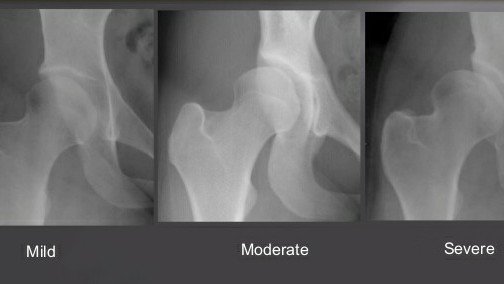

June has been an incredibly busy month. It was Hip Dysplasia Awareness Month which I have been busy supporting - holding fundraising events, completing charity challenges with other Hip Dysplasia sufferers, doing radio interviews and spreading the awareness of a condition that has plagued my life and so many others.